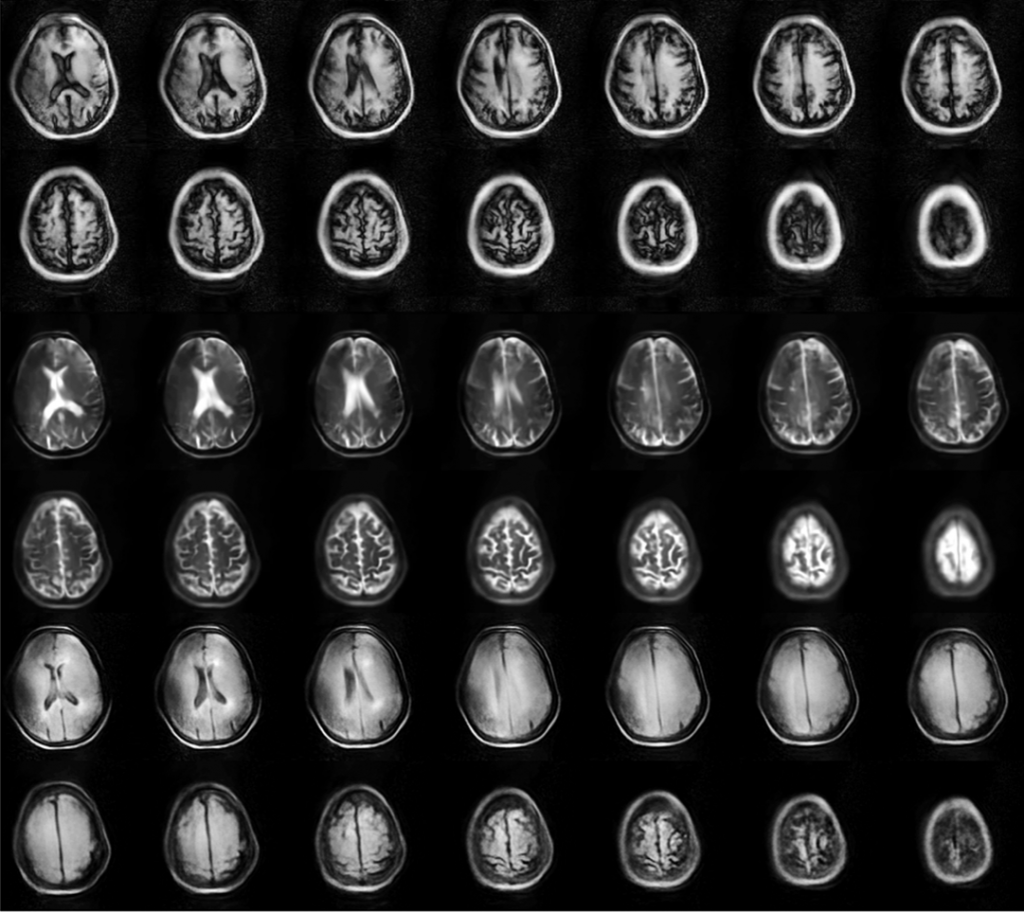

- High-Resolution Imaging

- Revolutionary Low-Field Technology Operates at just 87 mT, delivering diagnostically valuable images through advanced spatial coding algorithms.

Brain Images